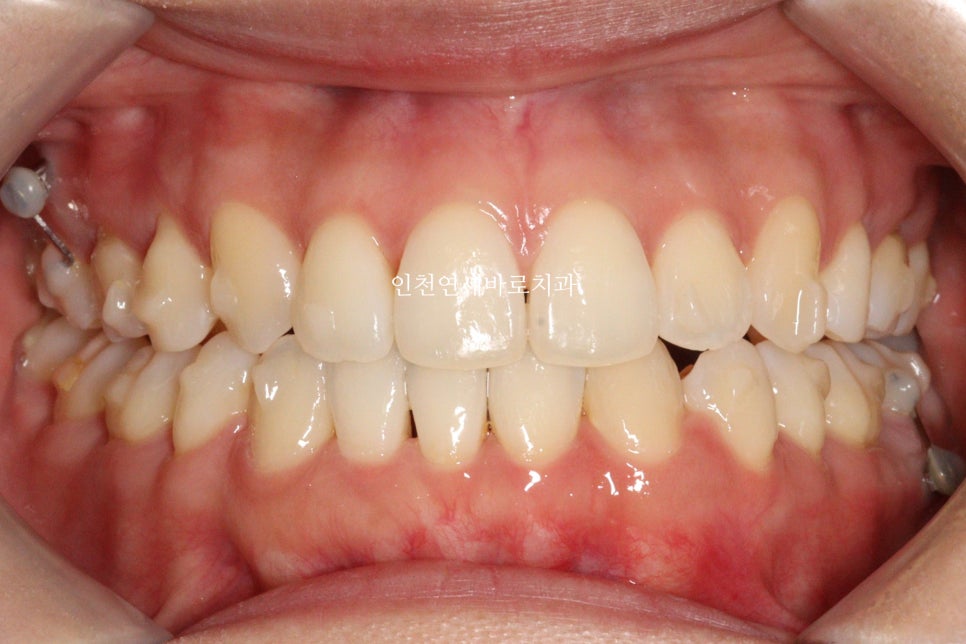

지난 주 마무리된 모습

결손치아가 있지만 교합은 문제없게 마무리

그리고 중요한 앞모습

과정이야 힘들고 오래걸리고 장치도 교체하고 어려웠지만

목표한바는 모두 달성한 치료입니다.